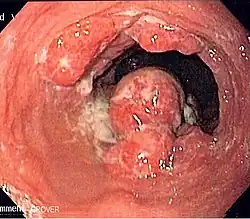

Ein Karzinom, wie es sich in der Endoskopie darstellt.

Die wichtigste Maßnahme zur Diagnosestellung ist eine Spiegelung (Endoskopie) der Speiseröhre. Diese wird meist im Rahmen einer kombinierten Ösophago-Gastro-Duodenoskopie (Spiegelung von Speiseröhre, Magen und Zwölffingerdarm) durchgeführt. Nachdem ein Betäubungsmittel verabreicht wurde, wird ein dünner, flexibler Schlauch in die Speiseröhre eingeführt. Von suspekten Bereichen werden dabei Biopsien entnommen und feingeweblich von einem Pathologen untersucht.